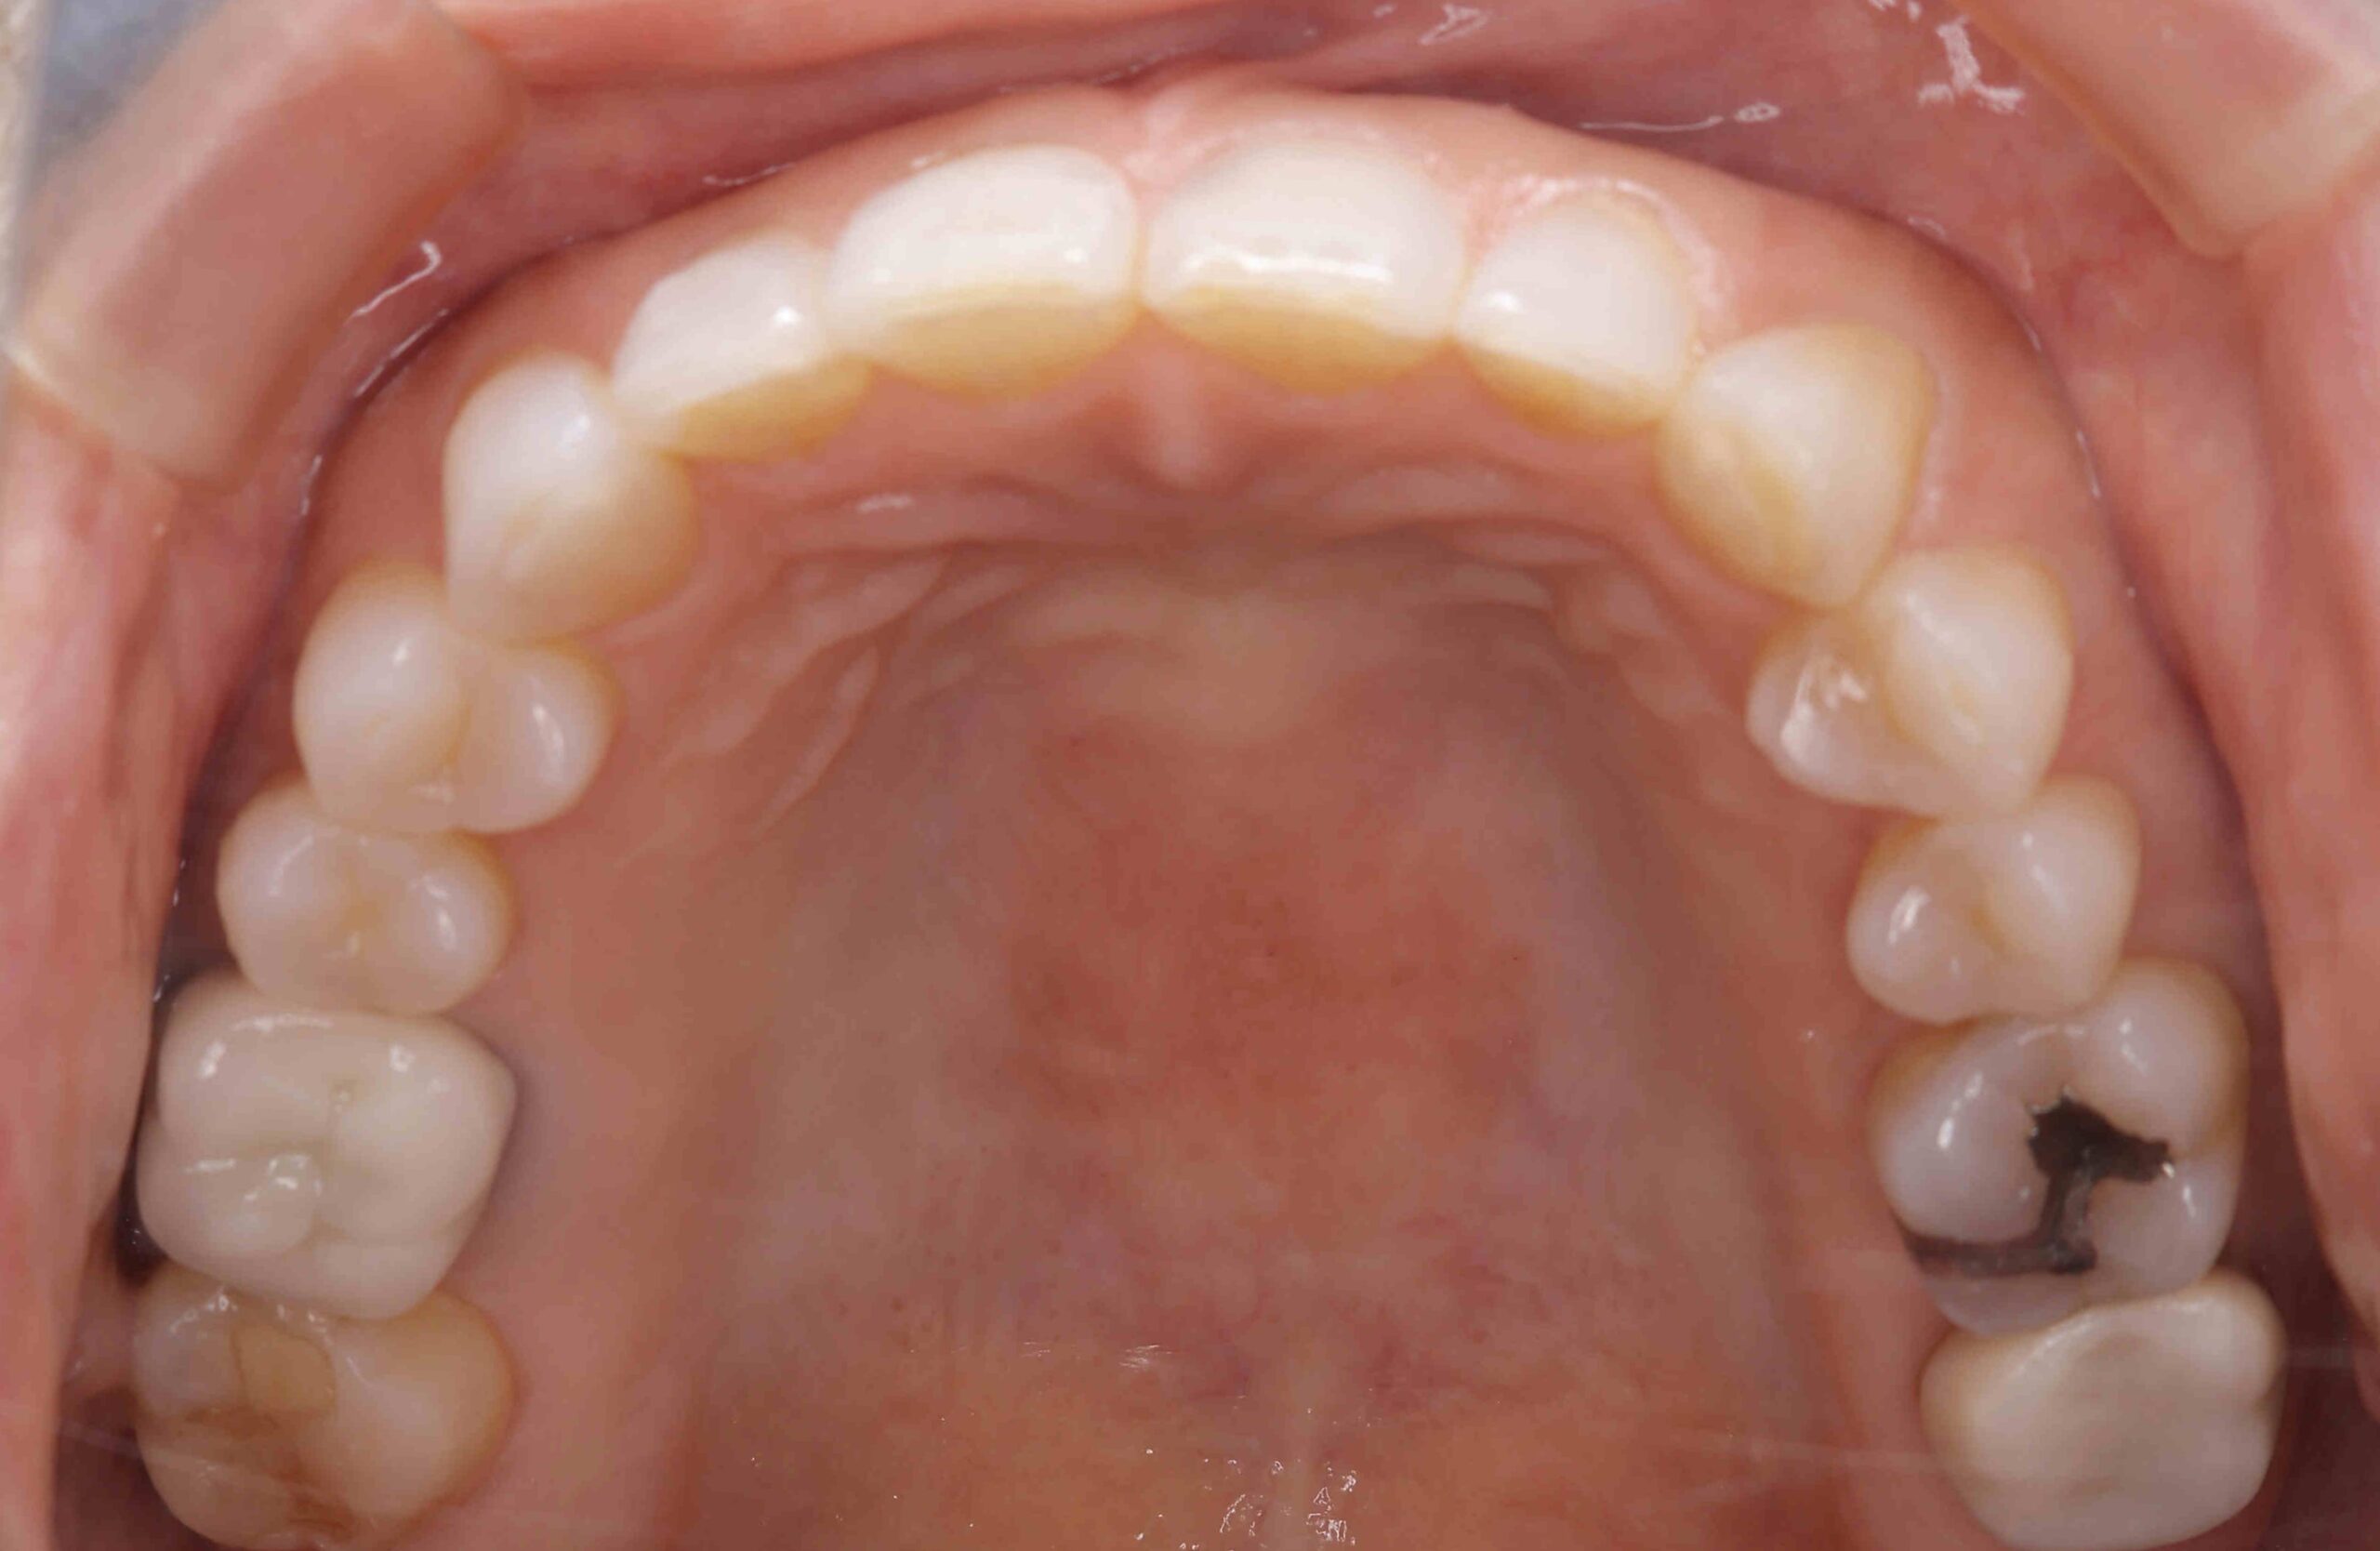

• 治療前

元々咬む筋力や食いしばり・歯ぎしりが非常に強く、『フレアーアウト』(前歯の歯並びが前方に放射状に倒れていく現象)によって「出っ歯」や「すきっ歯」の状態になっていました。

今回はご希望のマウスピース矯正で、食いしばりや歯ぎしりによる歯の破折やすり減りを予防しながら、歯と歯の隙間が広がって傾斜した前歯を元の位置に戻しました。

元々入っていた臼歯のブリッジは治療せず、そのままの位置で矯正を行うことを希望されたため、正中(上顎と下顎の中心線)を合わせることは難しいですが、美しい歯列と口元へ仕上がりました!